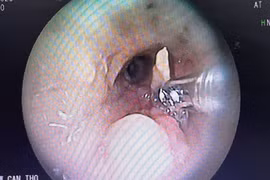

Sau khi lấy mảnh xương vịt ra khỏi phế quản, bệnh nhân mới nhớ lại cách đây khoảng 2 năm có hóc xương và khoảng 1 năm trở lại đây, ông bị ho dai dẳng, đau ngực kéo dài, viêm phổi nặng tái phát nhiều lần.

Chiều 15-3, PGS.TS.BS Trần Minh Trường, Phó Giám đốc Bệnh viện Chợ Rẫy cho biết, đơn vị này vừa thực hiện thành công gắp dị vật đường thở rất khó thực hiện bởi trong quá trình thực hiện nội soi bệnh nhân đã ngưng thở 4 lần, tụt huyết áp.